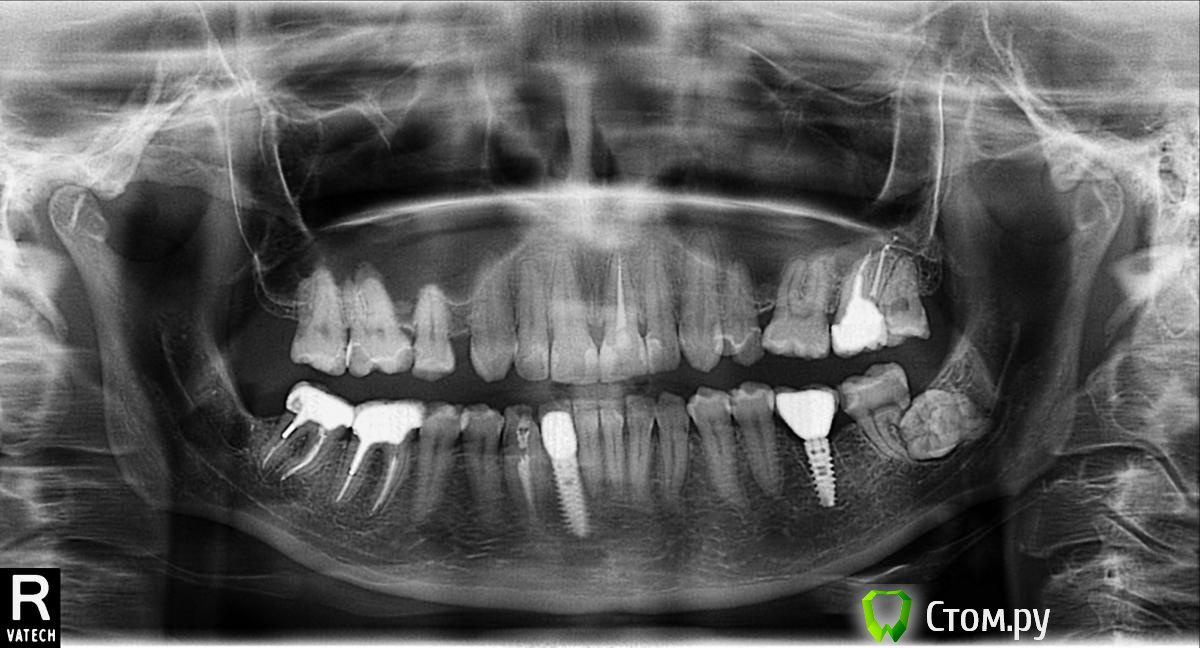

englishlady Опубликовано 13 декабря, 2013 Поделиться Опубликовано 13 декабря, 2013 Уважаемые врачи, здравствуйте.У меня осталась только одна восьмерка, но она находится в кости и , скорее всего, не прорежется. С другой стороны тоже была такая же восьмерка, но ее удалили в прошлом году. В последнее время зубы внизу слева немного ноют, все врачи, у которых я была, связывают это с восьмеркой. Надо ли ее удалять или есть большой риск повреждения нерва? На одном из форумов мне сказали, что восьмерка резорбировала корень 37 зуба.По мнению врача надо удалять оба зуба (37 и 38). Он написал, что еще возможна гемисекция с установкой коронки на 37 зуб. Выкладываю панорамный снимок. Он недавний, хотя н нем еще есть 28 зуб. Мне его удалили 2 месяца назад. Ссылка на комментарий

diesel87 Опубликовано 13 декабря, 2013 Поделиться Опубликовано 13 декабря, 2013 Нижняя левая восьмерка повернута в сторону щеки по снимку и есть шанс того что она просто накладывается на корень седьмого зуба, я бы удалил 38 зуб, риск повредить нерв почти отсутствует, но КТ при планировании не помешало бы. Ссылка на комментарий

englishlady Опубликовано 26 декабря, 2013 Автор Поделиться Опубликовано 26 декабря, 2013 Здравствуйте еще раз. Сходила к еще одному хирургу по поводу 38 зуба. Он посмотрел КТ. Предложил или ничего не делать или депульпировать 37 зуб с последующим удалением 38, поскольку на КТ увидел, что 38 зуб резорбировал один из корней 37 зуба. Даже еще предположил, что зубы ноют из-за кариеса на контактной поверхности 37 зуба, но это мне кажется сомнительным. У меня теперь еще больше вопросов, чем ответов.Если позволите, то я их Вам задам.Возможно:1) депульпировать 37 зуб, но не удалять 38, поскольку я боюсь, что 37 удалится вместе с ним?2) если зубы успокоятся, то ничего не делать ни с 37, ни с 38. А когда 37 будет уже не жилец, то поставить вместо него имплант, не трогая 38. Или рано или поздно на 38 возникнет кариес или киста? И тогда придется все это удалять вместе с кистой. Или этого не произойдет, поскольку 38 зуб находится в кости? Хочется обойтись малой кровью.Извините за дотошность.Срезы, по которым врач сделал эти выводы, выкладываю.http://http://s020.radikal.ru/i718/1312/6b/8910406e280a.jpg Ссылка на комментарий